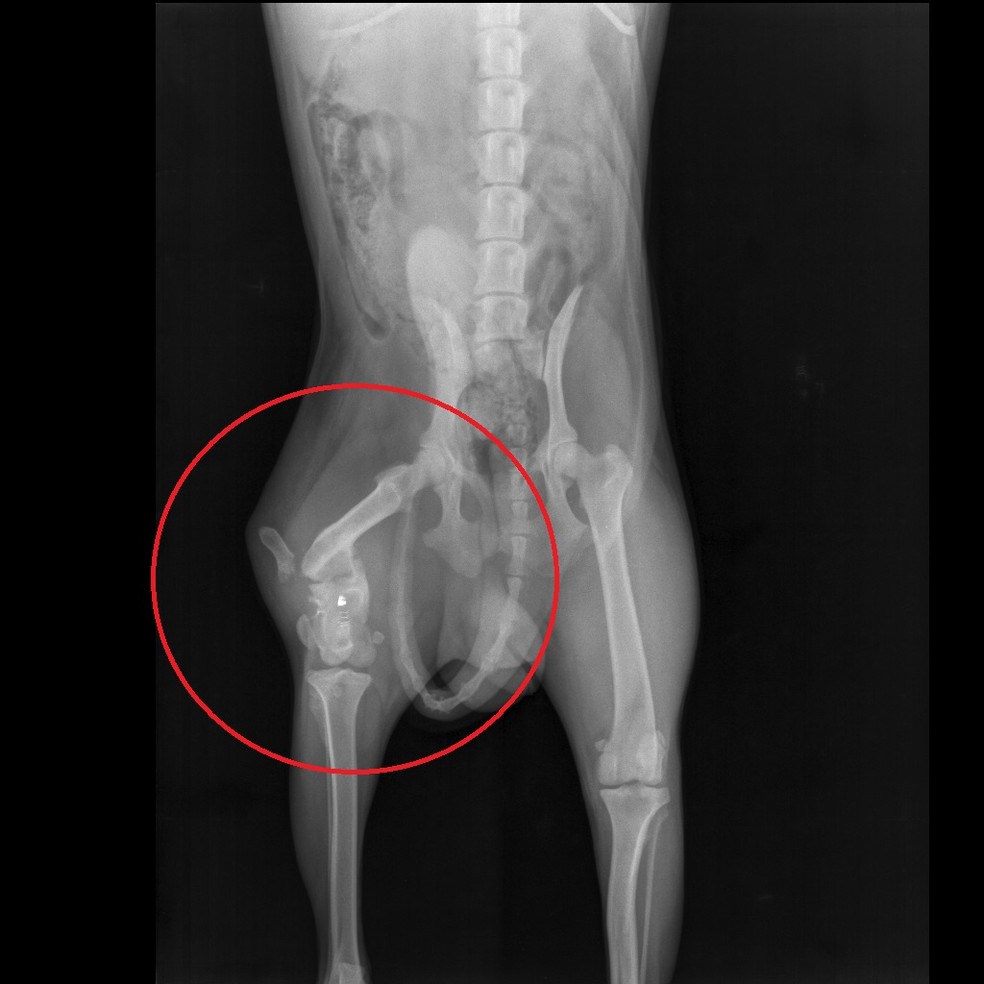

Com o exame de Raio-X de coxa estudam-se condições como fraturas luxações processos inflamatórios tumores e desgastes ósseos além de servir para avaliação e seguimento após procedimentos cirúrgicos. Raio x da pelve mostrando fratura do fêmur direito. Sempre que existir suspeita de uma fratura é muito importante ir rapidamente ao pronto-socorro para fazer um raio X e identificar se realmente existe alguma quebra nos ossos que precise ser tratada.

Raio-X - A forma mais comum para se avaliar uma fratura que fornece imagens claras dos ossos. Se um raio-X das articulações do quadril for realizado de acordo com Launstein Lauenstein a posição do paciente é a seguinte. Raio-x de ambos os quadris fratura do fêmur.